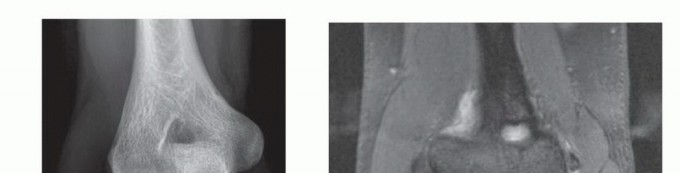

DEFINITION Panner Disease Panner disease is a condition in which there is compromised subchondral bone, poten…